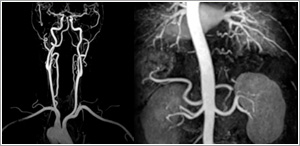

MR Angiography (MRA)

This technique uses flowing blood to obtain detailed images of the blood vessels. The examination is fast and easy to do, and produces images that approach the quality of traditional invasive catheter angiography.